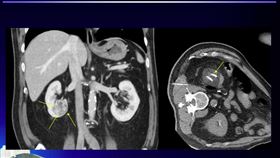

腹痛就醫竟腎癌!北榮「凍」死老翁癌細胞

今年73歲郭先生,61歲時半年內出現三次半夜腹痛,意...

2024/03/22 09:10